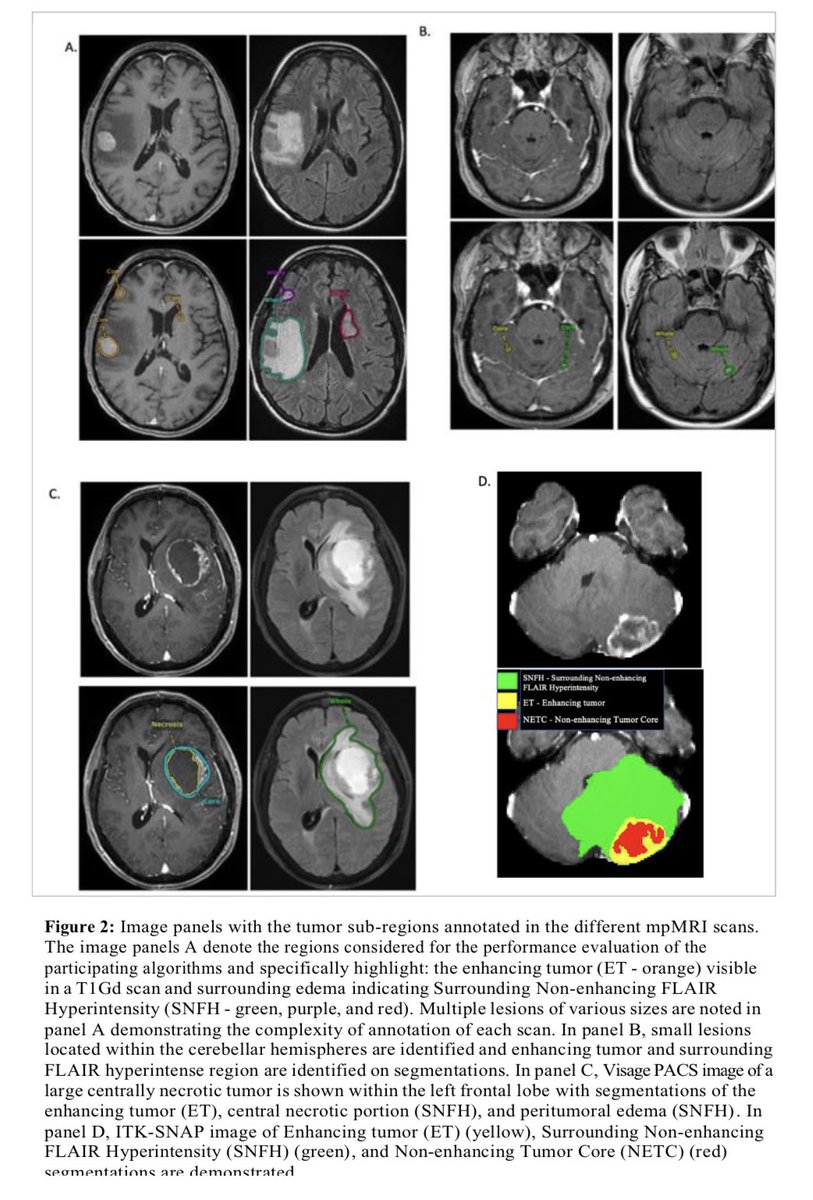

A Large Open Access Dataset of Brain Metastasis 3D Segmentations with Clinical and Imaging Feature Information https://t.co/0jyX0F4ZJY Exciting work led by @DivyaRamakris19 #ImagineQuant #OpenScience #BrainMets @BraTS_challenge #segmentation #collaboration #radtwitter

(2/2) ..don’t forget that you can still review the scientific abstracts on #Whova among which is also our work on PACS-based autosegmentation of brain metastases (BM) and ML-based BM classification. Grateful to have a mentor like @MariamAboian to make work like this possible 🙏